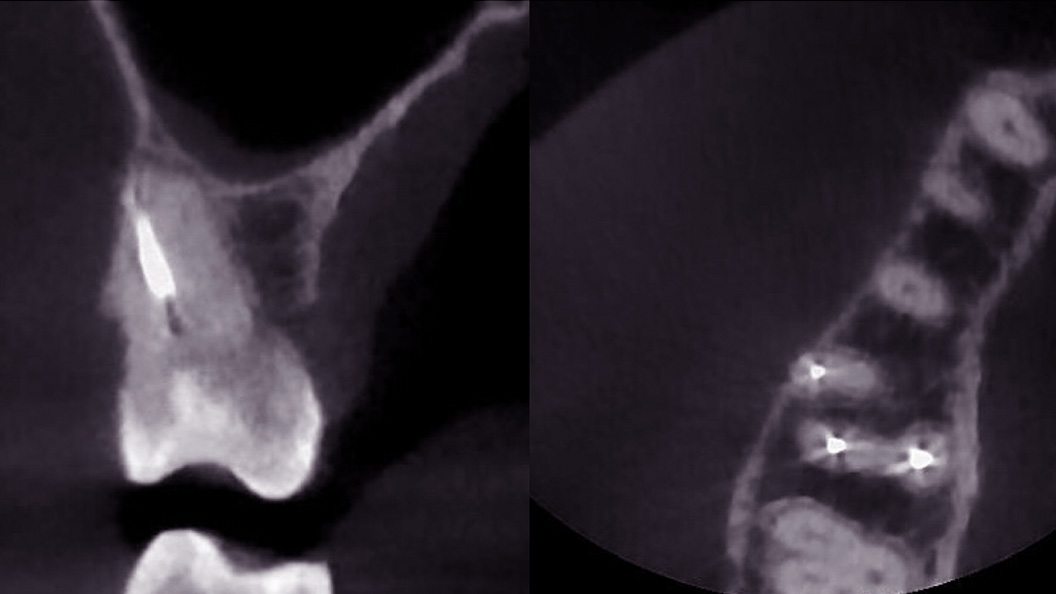

Пациентка после лечения в другой клинике обратилась в «Стоматологию Комфорта» с жалобами на ноющие боли в области жевательных зубов верхней челюсти. Боли усиливались при принятии пищи и горячих напитков. В результате проведения конусно-лучевой компьютерной томографии врач Вахлюева Елена Сергеевна обнаружила пропущенный дополнительный канал в ранее леченом моляре. Проведено селективное эндодонтическое лечение с пломбированием зуба.

- проведение конусно-лучевой компьютерной томографии и выявление проблемы;

- селективное эндодонтическое лечение зуба 1.6;

- пломбирование канала зуба.